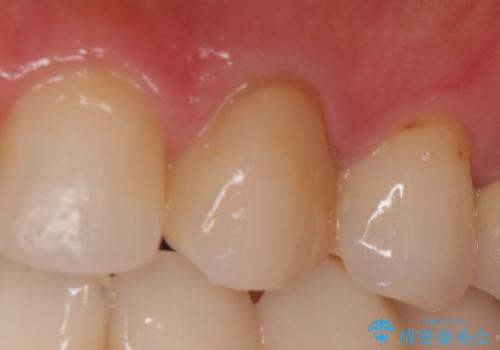

- 根管治療後歯が黄色くなってきたのでセラミックにしたいといらっしゃった方の症例です。

再根管治療後、オールセラミッククラウン(スペシャル)による補綴を行いました。

前歯の補綴ではオールセラミッククラウンを希望される患者様が多いですが、オールセラミッククラウンの中でも、エコノミー、スタンダード、スペシャル、エクセレントとランクがあります。

その中でも特に審美性が高いのがスペシャル、エクセレントです。スペシャル、エクセレントは口腔内写真をもとに熟練の技工士が、患者様の口腔内に合わせたオーダーメイドのクラウンを製作致します。